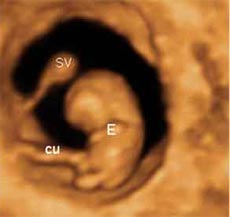

El bebé ha crecido de forma espectacular dentro del útero materno en la semana 8 de embarazo. Mide entre 10 y 14 milímetros. A partir de esta semana, para los médicos ha dejado de ser un embrión y ha "ascendido" de categoría de feto, y así será hasta el final del embarazo.

- La cabeza del niño es muy grande en proporción al resto del cuerpo y siempre está inclinada sobre el cuerpo.

Las vértebras en formación se han colocado alrededor de la médula espinal para constituir la columna vertebral. Ya se aprecia un esbozo de lo que serán los pulmones y se han empezado a formar los riñones y el resto del aparato urinario.

Sus brazos y piernas se han alargado y las palas, que se convertirán en manos y pies, se van separando del resto del cuerpo y aparecen en ellas unas hendiduras que dejan entrever lo que serán sus dedos.

Los intestinos empiezan a ser demasiado largos para el diminuto cuerpo que tiene el bebé, así que siguen su desarrollo fuera del abdomen dentro de un saco adyacente al cordón umbilical.

Éste es muy grueso con respecto a las dimensiones del feto, y es que si hasta ahora se alimentaba del saco vitelino, a partir de esta semana el bebé recibe los nutrientes y el oxígeno de la placenta. Se trata de un órgano vital en el embarazo, que nace y muere con la gestación. Sin ella el embarazo no es posible que siga adelante, y cualquier alteración placentaria lo pone en un grave peligro.